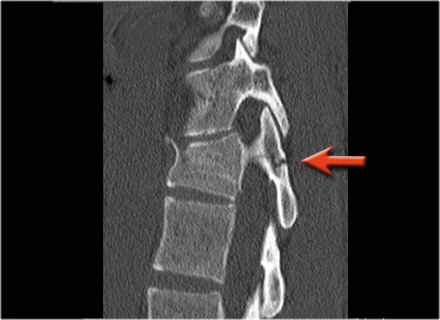

The findings are:

- The main feature is posterior distraction with horizontal fractures of posterior elements (red arrow)

- Avulsion of a spinous process (yellow arrow)

- Widening of facet joint (green arrow)

- Burst-type fracture

In this case some would call this a burst fracture with PLC-injury i.e. 2+3 points.

However the distraction is the most important finding, i.e. distraction and PLC injury, i.e. 4+3 points.